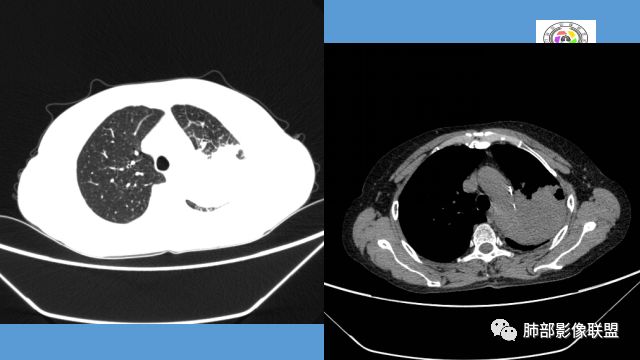

1.双肺多发病灶,结节影、树丫影,边缘分布……病灶符合继发性肺结核。

2.左肺上叶大片实变影,密度不均,体积轻度增大,注意轻到中度强化及血管影未见破坏、未见坏死空洞……病灶更符合炎症,而不大支持干酪性结核及肺鳞癌等,后两者的破坏能力是比较强的。

3.支气管阻塞,沿途可见钙化及液性潴留……更符合支气管内膜结核。

综上,双肺继发性肺结核诊断应当成立;左肺上叶大片影,以支气管内膜结核伴阻塞性炎症解释更为合理。